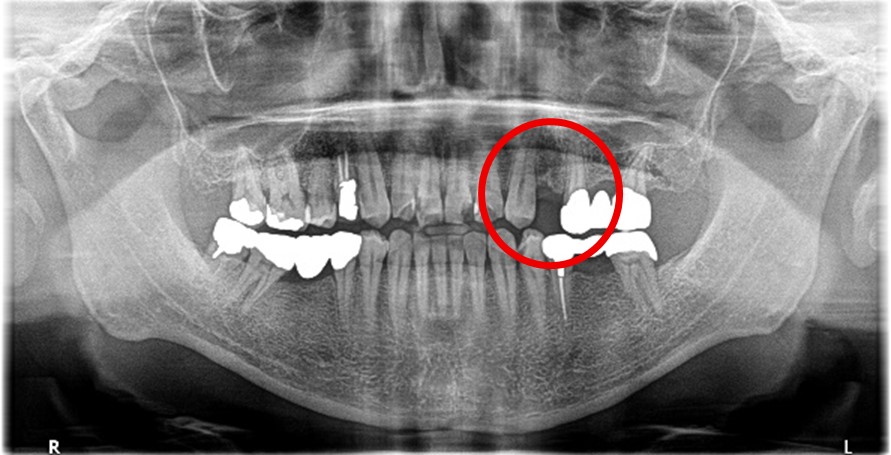

Before

※赤丸を抜歯しました。